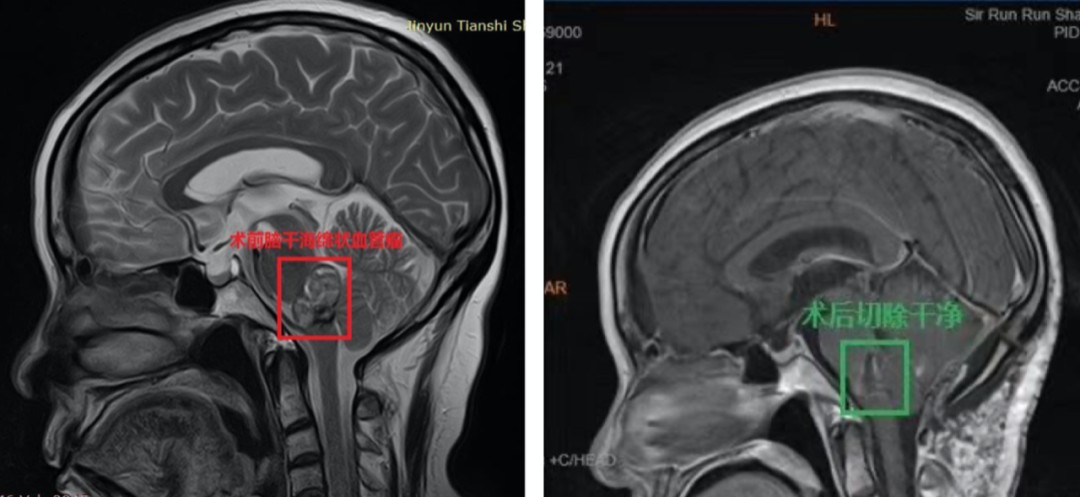

1、术前诊断:脑干脑桥海绵状血管瘤,6次脑干出血活动期,压迫四脑室

术后48小时内MR复查显示肿瘤全切